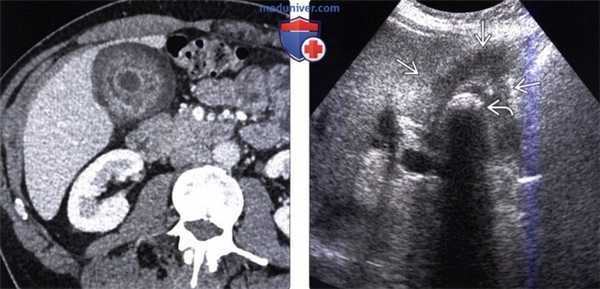

(Слева) На аксиальной КТ с контрастным усилением определяется рак желчного пузыря с инвазией в печень и нисходящую часть двенадцатиперстной кишки. Такие опухоли, если признаются резектабельными, однозначно требуют выполнения расширенной холецистэктомии и радикальной резекции.

(Справа) На аксиальной КТ с контрастным усилением визуализируется объемное образование в ямке желчного пузыря, прорастающее в печень. Во многих случаях, в том числе и в этом, место происхождения опухоли сложно определить.

(Слева) На аксиальной КТ с контрастным усилением определяется распространенное круговое утолщение стенки желчного пузыря, которое проспективно было расценено как проявление ксантогранулематозного холецистита. Тем не менее, во время оперативного вмешательства обнаружился рак желчного пузыря.

(Справа) На сонограмме визуализируется объемное образование в ямке желчного пузыря и конкрементдающий акустическую тень. Образование не отделено от прилежащих отделов печени. На КТ (томограммы не продемонстрированы) была обнаружена локальная инвазия рака желчного пузыря в центральные отделы печени.